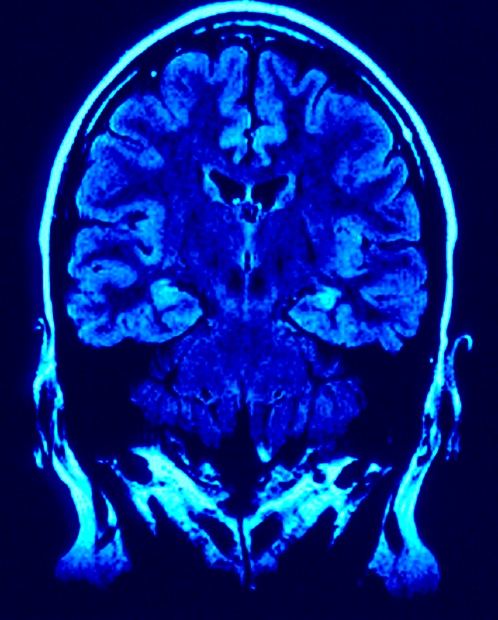

¿Cuántos secretos se esconden en ese laberinto de conexiones sin fin?

Si la Ciencia tuviera que tener un símbolo, yo escogería éste de arriba que nos señala el lugar donde habita la Mente, dónde se fraguan las ideas. Una configuración de átomos de energía donde residen todos los secretos del Universo, toda vez que, la podríamos considerar la obra suprema del Universo